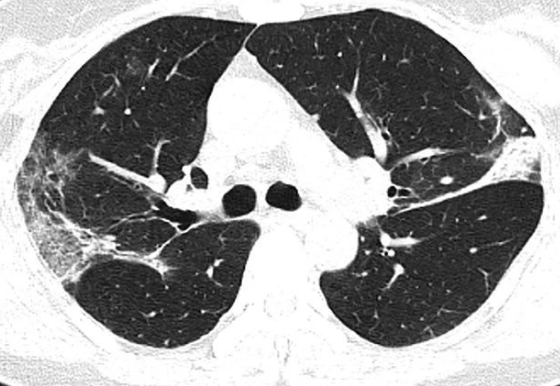

Tổn thương kính mờ trên phổi được biểu hiện bằng màu đỏ.